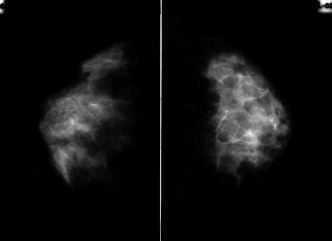

Paciente de 32 años con hallazgo de una adenopatía axilar izquierda de un mes de evolución, sin nódulo mamario palpable. Las mamografías no evidenciaban lesión mamaria sospechosa (Figs. 1 y 2). La adenopatía fue puncionada, siendo positiva para malignidad y sugestiva de neoplasia epitelial de origen glandular. Se realizó estudio de extensión de carcinoma de mama sin hallazgos de interés. Decidimos realizar una RNM mamaria, observándose un área de hipercaptación de contraste en el cuadrante superoexterno de la mama izquierda, sin que se pudiera precisar si correspondía a cambios inflamatorios, mastopáticos o neoplásicos.

Figura 2. Mamografía bilateral proyección craneocaudal.